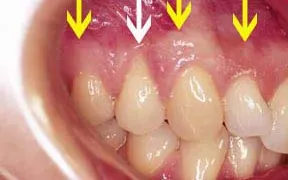

Periodontal Gallery Case 5

This patient is missing a lot of gum tissue around the neck of the tooth with the white arrow.

The yellow arrows are pointing to the line of healthy attached tissue, You can see how much space there is between the yellow arrows and the neck of the tooth.